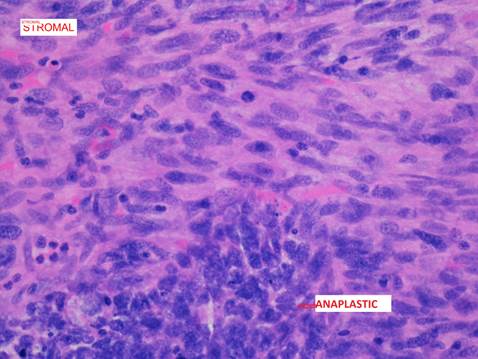

A preliminary diagnosis of renal cell carcinoma was made based on the clinical findings and investigations. The patient underwent open radical right nephrectomy, retroperitoneal lymph node dissection and partial excision, and reconstruction of vena cava. The renal samples were sent for histopathology. The right kidney specimen (with fibro adipose tissue) weighed 1291 g and 175 × 140 × 110 mm in size. The tumour was located in the mid-pole and lower pole of approximately 100 × 95 × 100 mm. On gross inspection, the tumour was cream and pink in colour with mixture of solid and cystic components (Figure 3). There was an extensive haematoma within the lumen of the cyst and possible necrosis. The retrocaval lymph node measured 4 cm. Histologically, the tumour comprised of blastemal, stromal and anaplastic elements. The blastemal elements were present in nodular fashion and had syncytial pattern with no diffuse infiltrative component (Figure 4). The anaplastic elements were focally present in stromal elements (nuclear sized 3× tumour cells and tripolar mitosis; Figure 5). The stromal elements were present with focal anaplastic elements. There were features of necrosis, haemorrhage and cystic degeneration. The morphologic and histopathology features favoured adult Wilms' tumour with synovial sarcoma as a differential diagnosis. A fluorescence in situ hybridization analysis showed loss of heterogeneity (LOH) for 1p 16q, which is associated with poor outcomes in paediatric Wilms' tumour. The pathological staging was pT3a, pN1 and cM0 (pT3a – tumour invading renal sinus fat but not beyond Gerota’s fascia, pN1 – metastasis in single regional lymph node, cM0 – not stated). The patient was subsequently treated with adjuvant combination chemotherapy and radiotherapy.

Figure 5. Microscopic features of adult Wilms’ tumour showing stromal elements and focal anaplastic elements.